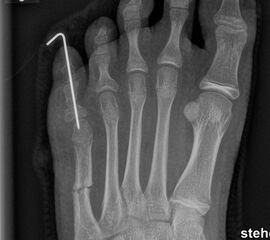

Zusätzlich schränken Wachstumsfugen die Wahl der Osteosynthese ein. Eine die Fuge kreuzende Osteosynthese ist ausschließlich mit Kirschner-Drähten möglich (Abb. 3).

Abb. 3 a-j: Beispiel einer Calcaneusverschiebeosteotomie mit offenen Wachstumsfugen und der entsprechenden Osteosynthese mit Kirschner Drähten. Lokalisation der Osteotomie (a), Lage der Fräse (b-d), Drahtlage mehrere Ansichten (e-h), Heilung der Osteotomie 4 Wochen postoperativ und Entfernung der Drähte (i-j).

Zum Lesen der Bildbeschreibung und zur Vollansicht bitte die Bilder anklicken. Bilder: A. Helmers.